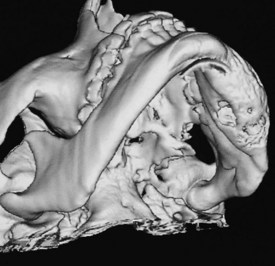

Three-dimensional reconstructions of CT images provide an excellent overview of the mandible or maxilla from any desired angle

• Three-dimensional reconstructions of the mandible of a patient with an ossifying fibroma of the body of the mandible on the left-hand side causing expansion and involving the lingual cortex are shown in the Figures

• A three-dimensional CT scan and a one-to-one reproduction of the CT scan:

• Are of great value to the surgeon for mandible reconstruction with a microvascular free flap